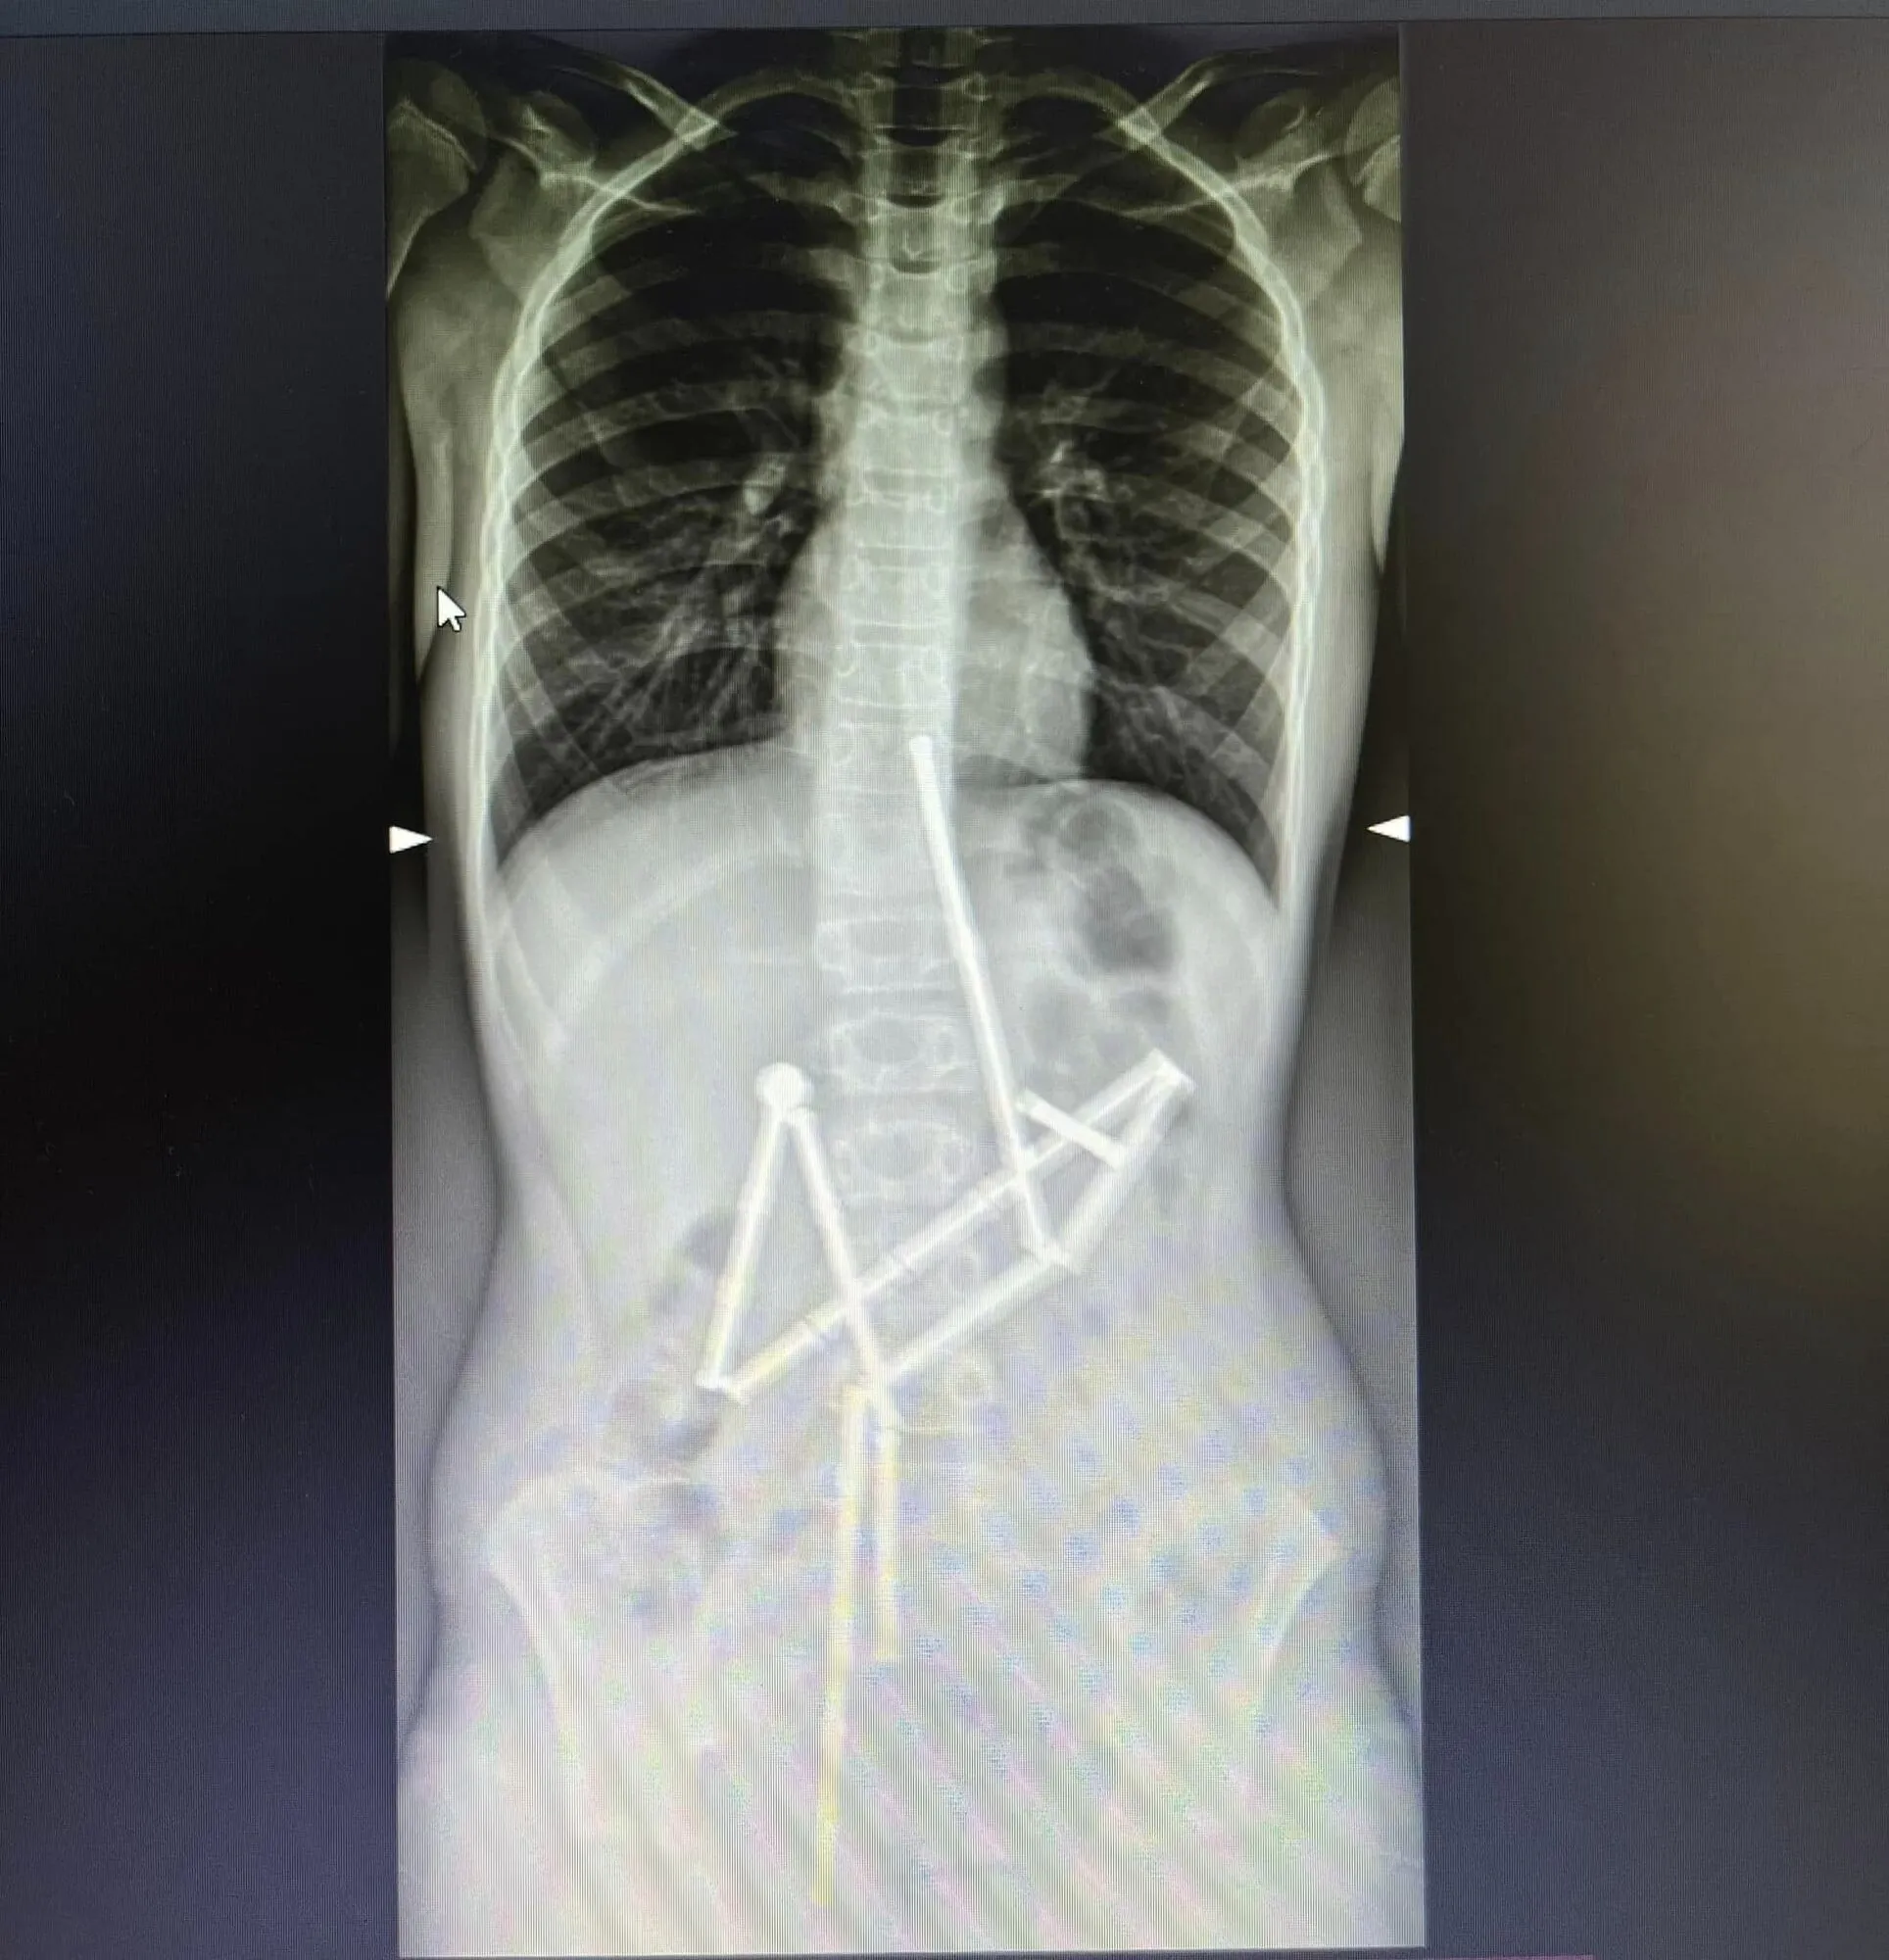

У Києві лікарі "Охматдиту" врятували дитину. Маленький хлопчик проковтнув 20 магнітів, що становило реальну загрозу життю малюка.

За словами лікарів, до них звернулися батьки дитини, що скаржилась на біль у животі. Вже на першому рентген-знімку спеціалісти побачили наявність у травному каналі цілої групи сторонніх тіл, в яких вдалось впізнати магнітний конструктор. 20 магнітів перебували у різних частинах шлунково-кишкового тракту, проте були з’єднані між собою.